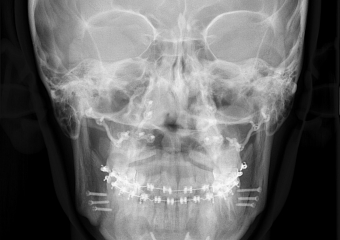

Telerradiografia frontal após a cirurgia - Clínica Cliniface

Telerradiografia frontal após a cirurgia